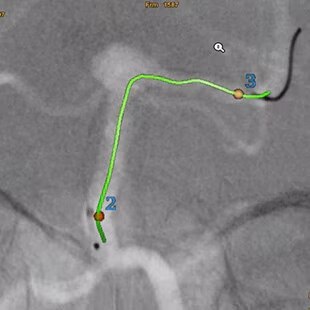

Guide

Select from the sub-volumes of vessels, centerlines, calcifications and landmarks to overlay on live fluoroscopy for 3D fusion guidance, with digital zoom, to guide recanalization.

Import segmented anatomy, centerline and landmarks and overlay them on live fluoroscopy on the frontal or lateral plane for 3D fusion guidance.